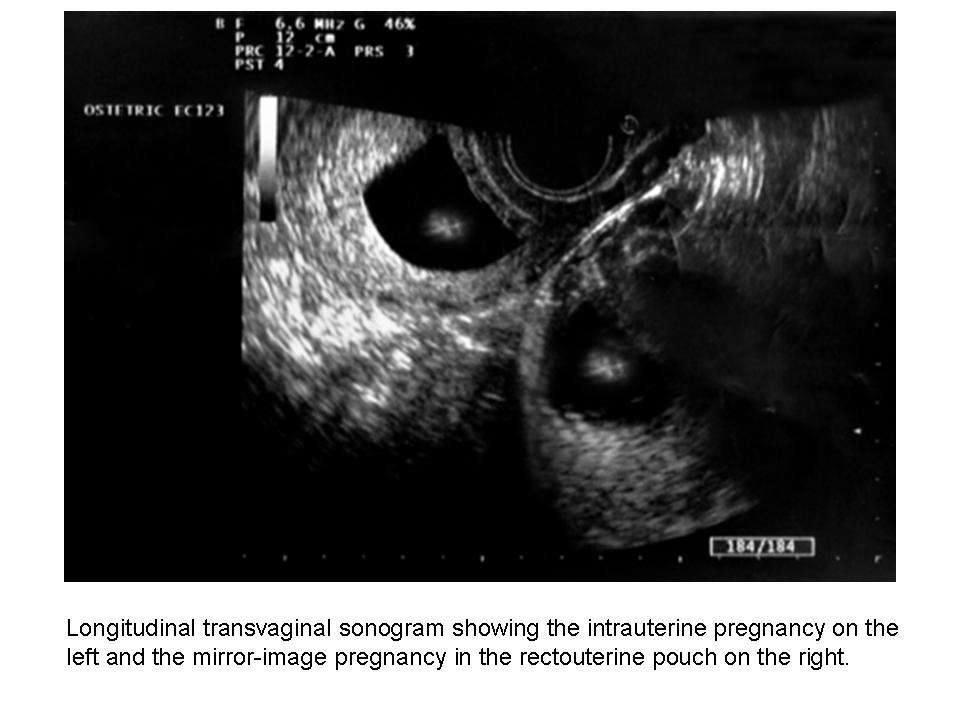

The patient underwent transvaginal sonography (MyLab 25; Esaote SpA, Florence, Italy), which showed an intrauterine pregnancy with a live embryo measuring 29 mm, consistent with a gestational age of 8 weeks 5 days. A second gestational sac with irregular and undefined boundaries containing an active embryo measuring 17 mm was depicted in the rectouterine pouch (Figure 1). Both ovaries were visualized as normal, and no pelvic free fluid collection was noticed during the scan. These findings were consistent with a diagnosis of heterotopic pregnancy.

In this case, the patient had no risk factors for this condition, with a previous uneventful pregnancy delivered at term and no history of pelvic surgery or disease. To confirm the diagnosis, the woman was asked to fill her bladder, and transabdominal sonography was performed. Interestingly, only the intrauterine gestational sac was found, with a normal appearance of the rectouterine pouch and no ectopic pregnancy detected.